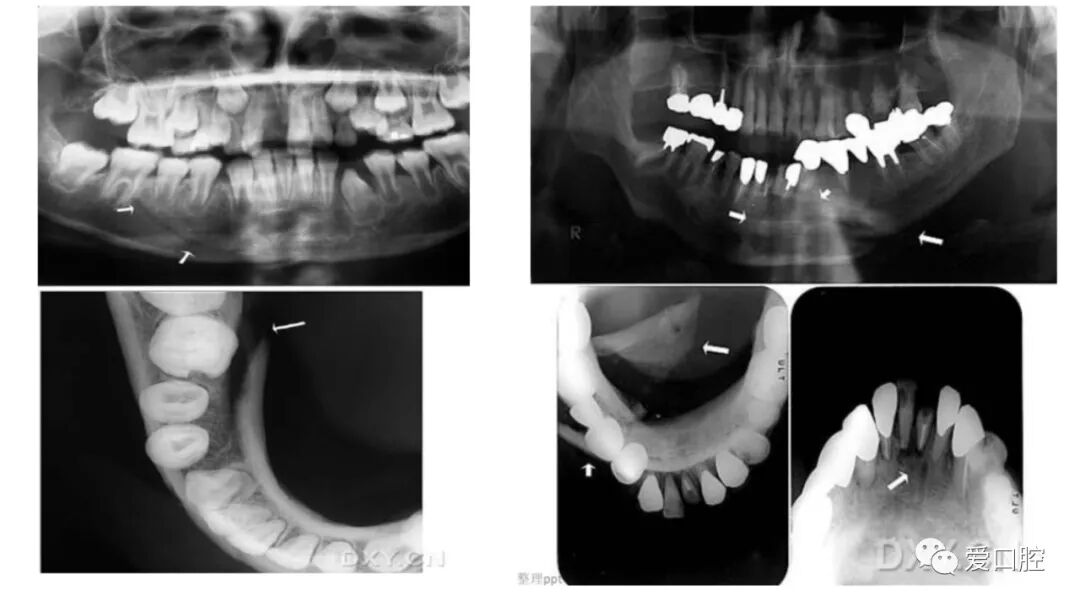

口腔小技巧 | 口腔科常见的病例影像!